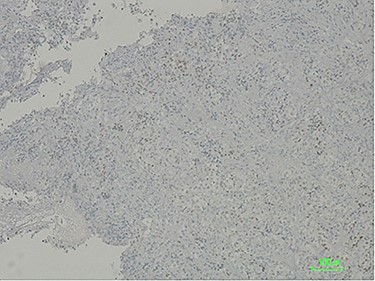

The histologic examination revealed a poorly differentiated adenocarcinoma, with a negative CDX2 and positive PAX8 immunostaining, hence compatible with a secondary lesion of endometrial origin (Figs 3 and 4).

CDX2 negative immunostaining excluding carcinoma of intestinal origin such as primary duodenal neoplastic lesion.

To this day, despite direct invasion being quite common, there have been very few reports of duodenal metastasis of malignancies originated in distant organs. Lung, renal, melanoma and colorectal cancer have sporadic reports of duodenal involvement [8, 9]. When identified on endoscopy, they frequently present as ulcerated lesions that can cause GI bleeding or gastric outlet obstruction. This finding is consistent with the endoscopy’s macroscopic description of the duodenal lesion and our patient’s clinical presentation. Immunohistochemistry provided the diagnosis after confirming its non-lower GI tract origin and gynaecologic related epithelial structure (positive for cytokeratin 7, negative CDX2 and positive PAX8 immunostaining) [3, 10].